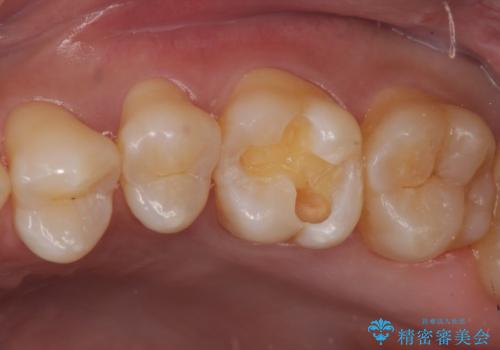

同じような樹脂の詰め物での治療ではまた虫歯ができることが予想されるため、今回はセラミックインレーで修復することとなりました。

- 左上6 セラミックインレー 77000円×1本費用は治療当時の料金となります

以前樹脂を詰めた結果再び虫歯ができてしまっていることから、同じ治療は同じ結果になる可能性があるため今回はアプローチを変えてセラミックインレーで修復処置をしていくこととなりました。

適合の良い修復物を入れることは今後の虫歯リスクを抑えることに繋がります。